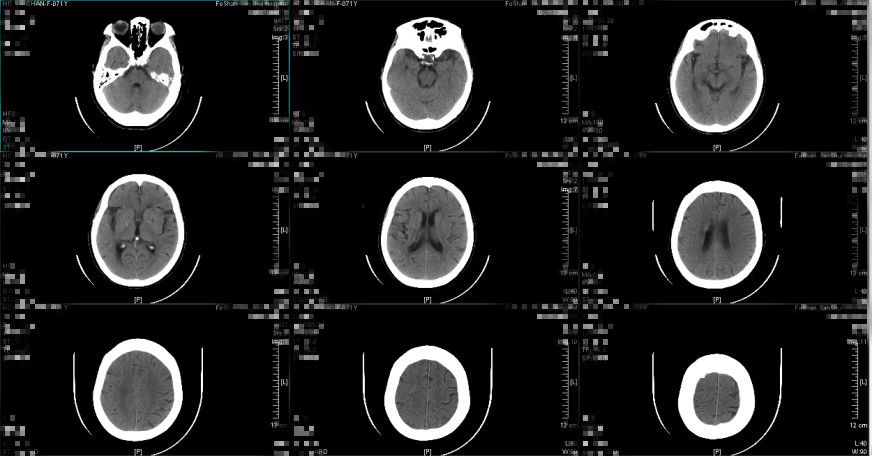

图5. 入院后第二天复查头颅CT提示:硬膜下血肿继续较前减少消散,中线结构大致居中。(2018-12-22 14:53:08)

图6. 入院后第九天复查头颅CT提示:亚急性硬膜下血肿形成,血肿量较前增多。(2018-12-29 15:36:23)

患者入院后第七天至九天诉头痛较前稍有加重,以夜晚为主,无呕吐,神志仍清醒,精神状态尚可,复查头颅CT提示亚急性硬膜下血肿形成,最大厚度约0.9cm,中线向左偏移约0.5cm,环池尚清晰,右侧稍有受压,评估有硬膜下血肿继续进展的趋势,考虑与患者年龄大、长期服用氯吡格雷抗栓治疗等因素有关,详细与患者及其家属讲解病情及治疗方案,选择予以立普妥药物治疗,拟治疗1周复查头颅CT,如继续进展予外科手术治疗,根据病情动态复查头颅CT检查评估颅内情况。